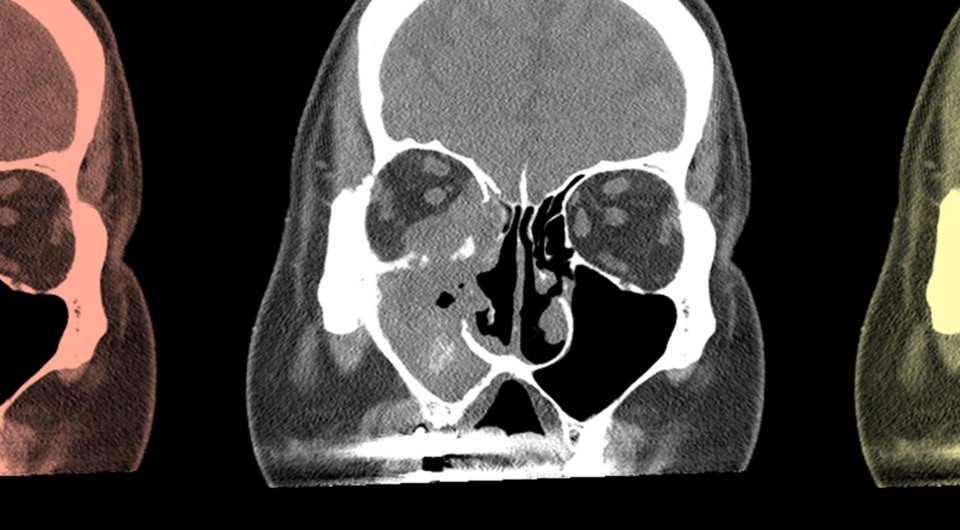

Острый инвазивный грибковый риносинусит считается потенциально опасным для жизни заболеванием, которое часто возникает у пациентов с иммунодефицитами. Инфекция развивается из-за инфильтрации слизистой оболочки носа и околоносовых пазух грибковыми организмами родов Aspergillus, Candida и Mucor и приводит к повреждению тканей, некрозу, а в тяжелых случаях — к распространению инфекции в другие органы.